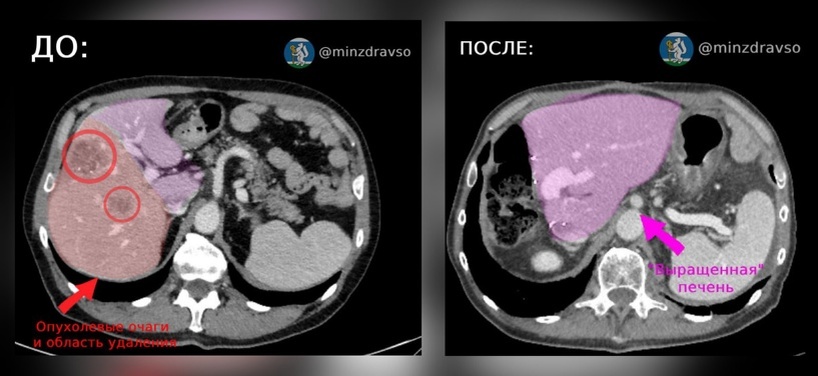

Онкологи удалили и вырастили пациенту новую печень

Врачи Свердловского областного онкологического диспансера помогли 60-летнему пациенту с раком печени. У мужчины удалили 50% пораженного органа. Медики закупорили ветви воротной вены, идущие к этой части печени, и помогли здоровым сегментам увеличиться в объеме, сообщили в пресс-службе регионального минздрава.

Основной метод лечения гепатоцеллюлярной карциномы (вид рака) — удаление части печение с опухоль. Это делают как открытым способом, так и лапароскопически, через небольшие проколы, рассказал заместитель главного врача по хирургии Свердловского онкодиспансера Глеб Кичигин.

По его словам, важно, чтобы оставшаяся часть печени могла компенсировать утраченные функции. Тогда орган сможет восстановиться. Возможность такой операции зависит от состояния печени, которая у большинства пациентов уже повреждена — чаще всего из-за гепатитов В и С, цирроза и других заболеваний.

Операция у 60-летнего пациента прошла успешно: печень восстановилась и справляется со своими функциями.